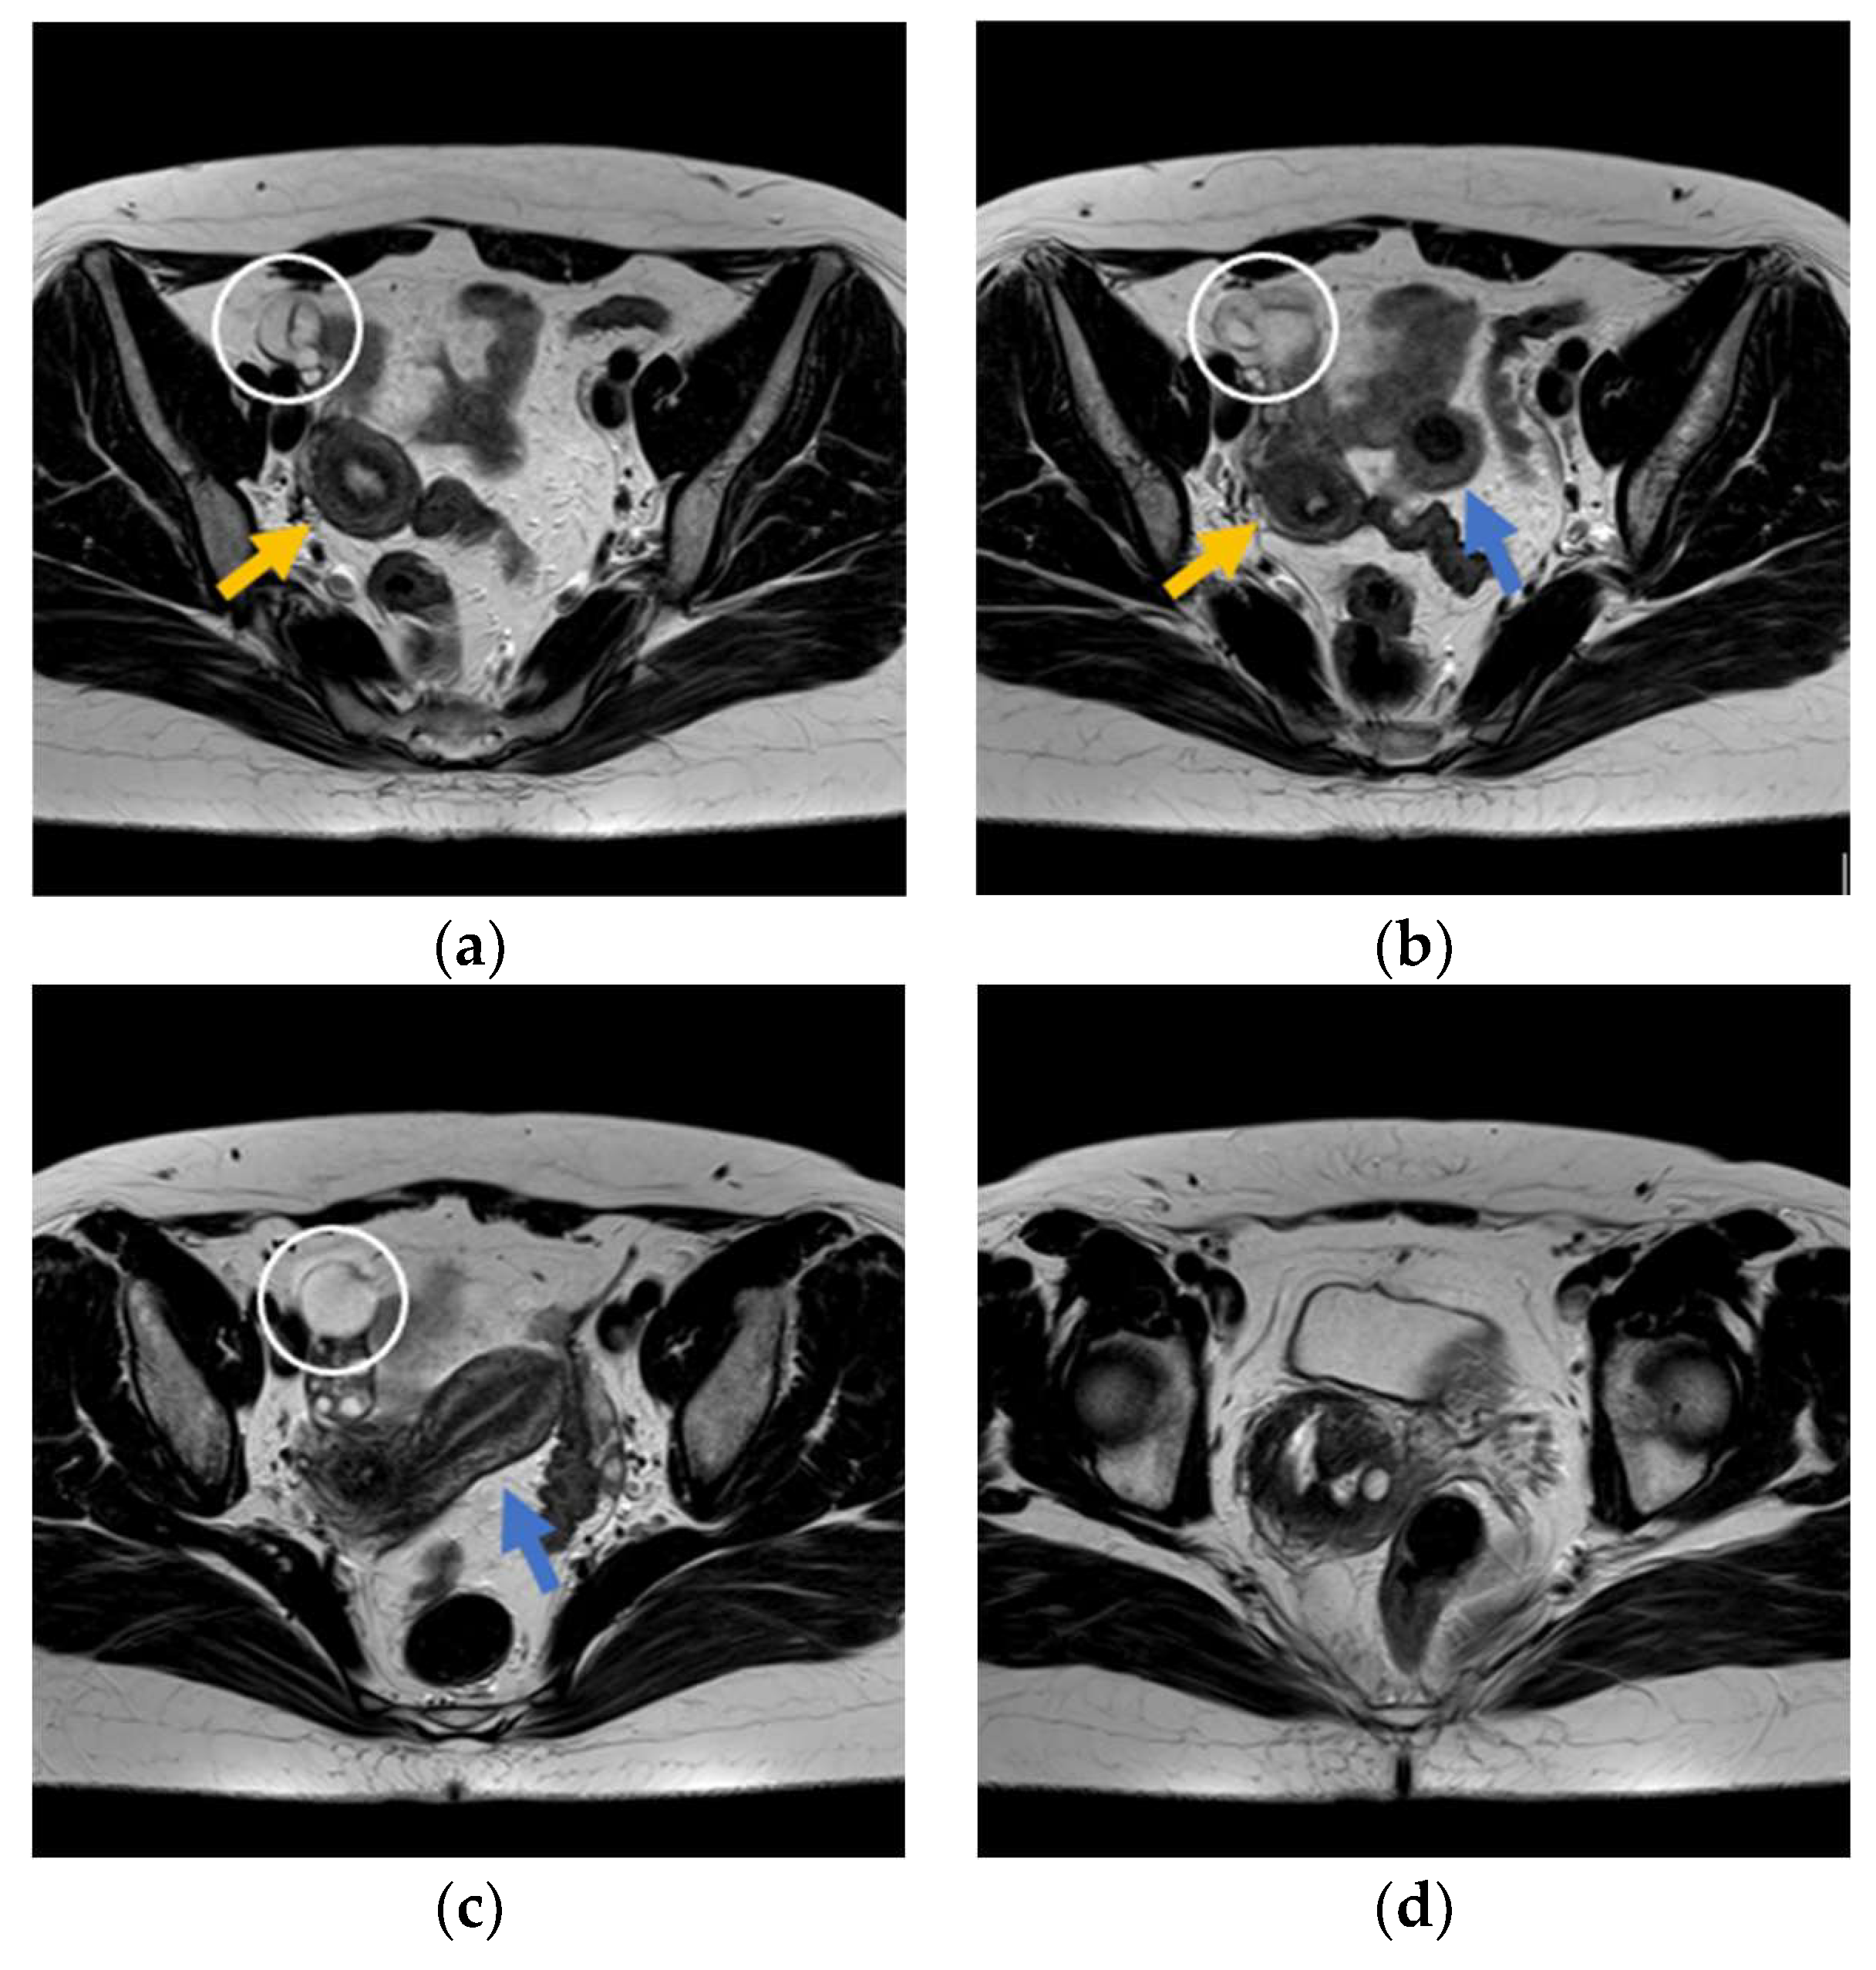

2. Case Presentation